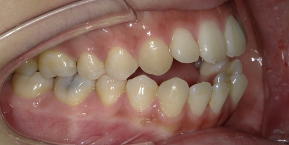

29才女性のビフォーアフター

| 診断 | 叢生(デコボコがある状態)、下顎前突、前歯部交叉咬合 |

| 治療方針 | インビザラインシステムにて主にIPR(歯と歯の間をわずかに削合してスペースを獲得する方法)を組み込んだ動的矯正治療を行い、叢生を改善後、保定を行う。臼歯部の咬合関係はプランの関係上維持して叢生と前歯部の咬合改善を目指した。 |

| 治療費 ※ | 70万8千円(診断、型取り、PMTC、保定装置を含む料金) |

| 治療期間 | 2年4か月 |

| リスク | 1日20時間以上マウスピースを使用できない場合、歯が動かない可能性がある。装着時や食事時に痛みを伴う。歯肉退縮や虫歯になるおそれがある。また、指導通りに装着できていない場合や適切なブラッシングが出来ていないとそのリスクが高くなる。歯根が短くなることがある。ごくまれに歯の神経が損傷してしまうことがある。過去にぶつけたり深い虫歯治療をしたことがあるとそのリスクはやや高くなる。矯正後には保定装置が必要。適切な使用ができない場合、後戻りの原因となる。将来的に歯並びが動いて再矯正が必要な場合がある。親知らずが正常に生えていない場合、その可能性がやや高くなる。 |